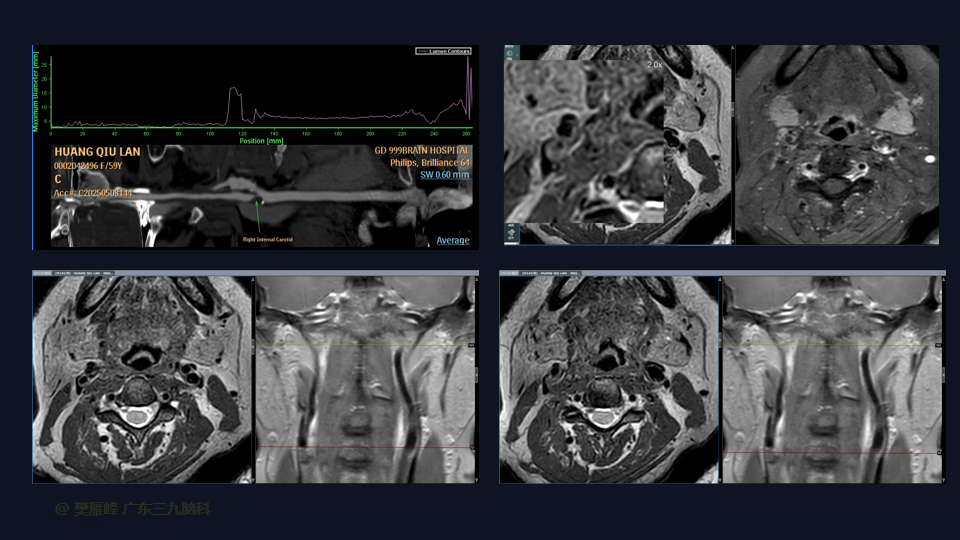

在这个二维手术视频中,展示了颈动脉内膜剥脱术(carotid endarterectomy,CEA)治疗严重的颈动脉动脉狭窄。患者是一名59岁的女性,有发作性言语不清、口角歪斜1周入院,MR血管高分辨平扫+增强+灌注成像示:1.右侧颈内动脉起始部管腔重度狭窄-接近闭塞,伴粥样硬化改变合并管壁斑块形成,并管壁轻度炎性改变;ASL检查右侧额颞顶叶及右侧基底节区多发低灌注影提示缺血改变,局部皮层区为主间杂多发高灌注影提示慢血流改变可能。经颅彩色多普勒血流图(TCD):左侧大脑中动脉中度狭窄,右侧颈内动脉虹吸段轻度狭窄。他接受了颈动脉内膜剥脱手术,手术顺利,术中造影显示血管通畅。术后一般情况尚可,无新发神经功能障碍,神经影像学显示血管通畅。术后继续康复治疗。术后3月复查DSA显示血管通畅。左侧鼻唇沟稍浅,左上肢肌力IV级、左下肢肌力V级-,右侧肢肢体肌力V级。我们展示了颈动脉的分离、斑块切除和颈动脉缝合的细微差别和技术要点。